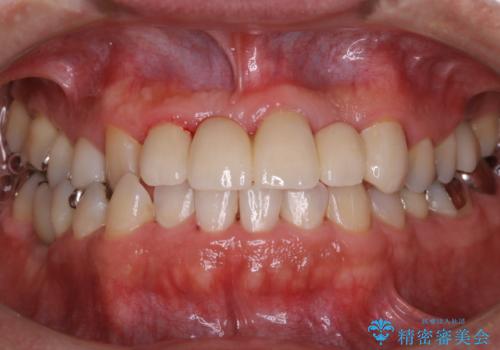

歯科衛生士によるPMTCでお口のケア

- 歯医者に来院することが久しぶりで、まずはクリーニングを希望とのことでした。コースや内容は、一番状態に合ったものでとのことだったため、PMTC60分コースを行いました。

PMTCとは「Professional Mechanical Tooth Cleaning」の略で、専用の機器を使った歯のクリーニングです。

審美的面だけではなく、歯周病や虫歯・口臭などのリスクを予防することができます。